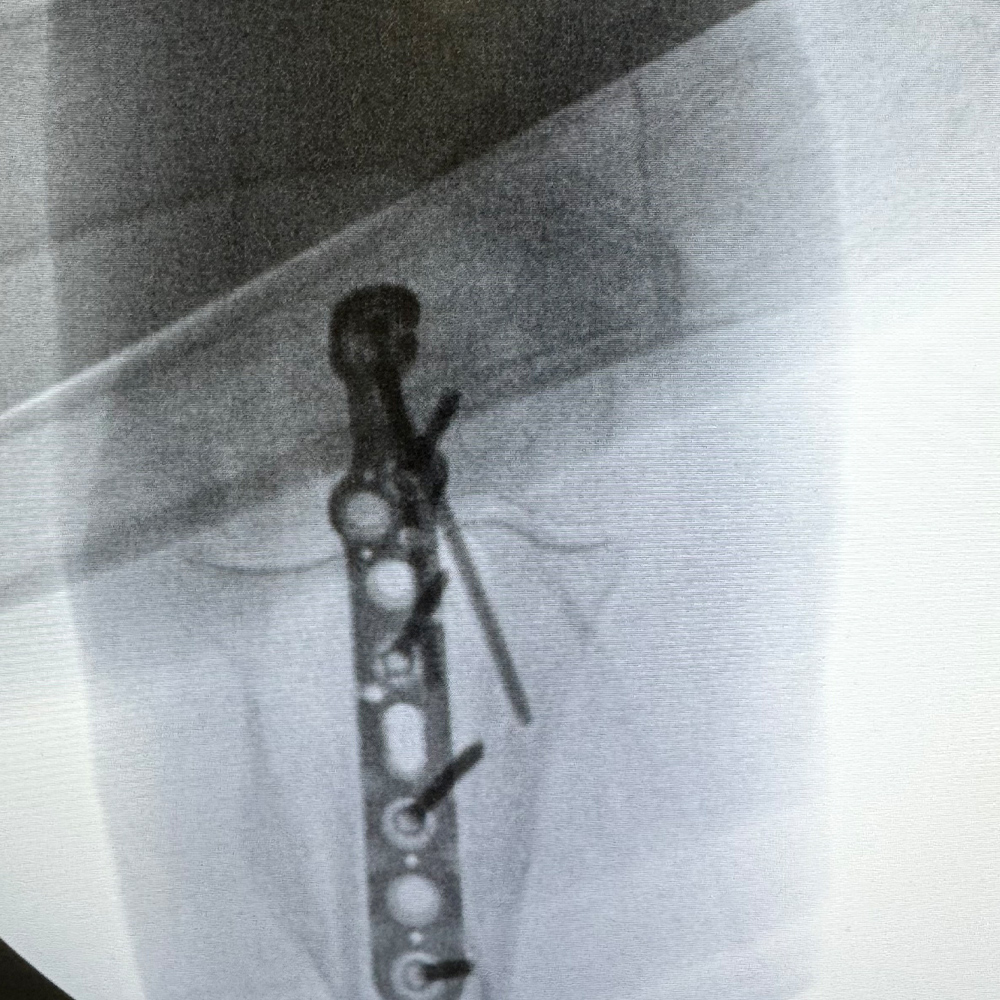

Midshaft Solutions

Plating System

- 40° Polyaxial locking

- Strong & consistent locking mechanism

- Low profile construct

- Titanium low-profile construct

- Locking caps allow all screws to compress the plate to bone before locking

- Locking caps improve fatigue properties and prevent screw back out

- Precise screw placement independent of plate position

- A single screw can be used to lag and then be locked into place without changing screw or disrupting reduction

- Polyaxial drill guides allows for provisional K-wire fixation

- The low profile design allows for optimal contour of the plate proximally